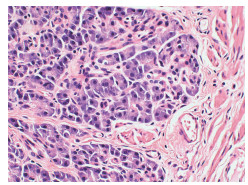

Expression of neural precursor cell expressed developmentally downregulated 4-1 in pancreatic cancer tissue and its clinical significance

Tingting BI, Sihui HOU, Yan LIU

2022, 38(3): 617-621. DOI: 10.3969/j.issn.1001-5256.2022.03.024

Abstract(1113) HTML (357) PDF (3129KB)(41)

Abstract:

Objective  To investigate the expression of the E3 ubiquitin ligase neural precursor cell expressed developmentally downregulated 4-1 (NEDD4-1) in pancreatic cancer tissue and its clinical significance.  Methods  Clinical data were collected from 58 patients who underwent surgical treatment in Xuzhou Central Hospital from January 2017 to December 2019 and were diagnosed with pancreatic ductal adenocarcinoma based on pathological examination. Immunohistochemistry was used to measure the expression of NEDD4-1 in pancreatic cancer tissue samples, and the association between the expression of NEDD4-1 and the clinicopathological features of pancreatic cancer was analyzed. Western blot was used to measure the protein expression level of NEDD4-1 in normal pancreatic ductal epithelial HPDE6-C7 cells and pancreatic cancer SW1990, BxPC-3, and PANC-1 cells. The t-test was used for comparison of continuous data between two groups, and the chi-square test was used for comparison of categorical data between two groups. The Kaplan-Meier method was used to plot survival curves, and the log-rank test was used for survival analysis. The Cox proportional-hazards regression model was used to investigate the factors associated with prognosis.  Results  The expression level of NEDD4-1 in pancreatic cancer tissue was significantly higher than that in adjacent tissue (79.31% vs 19.05%, χ2=35.614, P < 0.01), and the protein expression of NEDD4-1 in pancreatic cancer cells was significantly higher than that in normal pancreatic ductal epithelial cells (P < 0.01). In the patients with pancreatic cancer, the expression of NEDD4-1 was associated with distant metastasis (χ2=5.089, P=0.040), tumor differentiation (χ2=9.071, P=0.003), and TNM stage (χ2=8.882, P=0.003). The patients with high NEDD4-1 expression had a significantly shorter mean survival time than those with low expression (13.61±0.95 months vs 22.22±2.20 months, P=0.001). The Cox regression analysis showed that NEDD4-1 expression (hazard ratio [HR]=2.312, 95% confidence interval [CI]: 1.010-5.295, P=0.047), degree of tumor differentiation (HR=2.981, 95% CI: 1.556-5.712, P=0.001), and lymph node metastasis (HR=2.144, 95% CI: 1.155-3.979, P=0.016) were independent risk factors for the prognosis of patients with pancreatic cancer.  Conclusion  There is a significant increase in the expression of NEDD4-1 in pancreatic cancer tissue and cells, and the high expression of NEDD4-1 is associated with poor prognosis. Therefore, it can be used as a prognostic biomarker and a therapeutic target for pancreatic cancer.